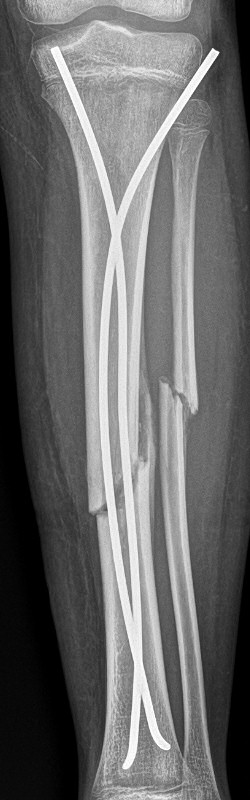

Tibia och fibula-frakturer, tibia spikats med 2 TEN-spik, sista 2 bilderna efter 5 veckor, då inte alls ömmande över frakturerna.